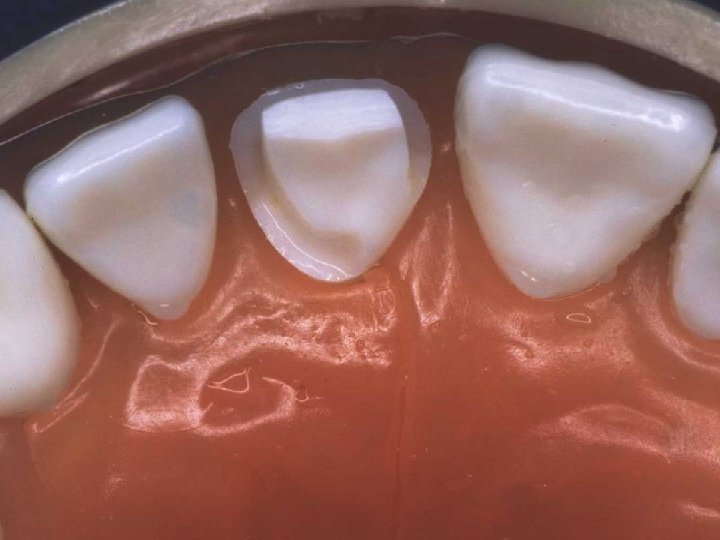

Lingual axial reduction

Axial wall and shoulder finishing